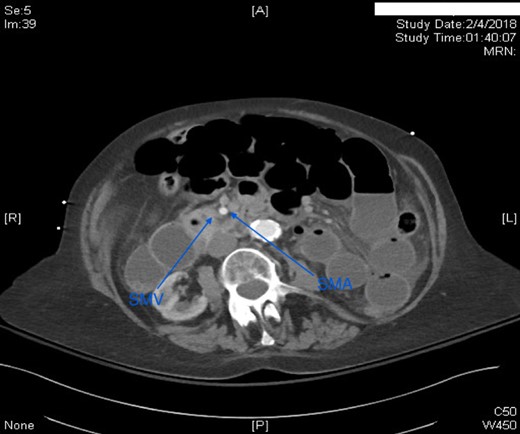

This case report presents an 80-year-old female with past medical history of Marfan syndrome with extensive cardiovascular manifestations including coarctation of the aorta, mechanical aortic valve and mitral valve replacement, heart failure with reduced ejection fraction (25–30%), and atrial fibrillation. The patient was admitted to the emergency general surgical service for complaints of acute onset colicky periumbilical abdominal pain, progressive abdominal distension, nausea and vomiting for 2 days. Emesis was described as non-bloody and non-bilious. Other pertinent history included one bowel movement 12 h prior to admission, which was non-bloody and inability to pass flatus for more than 24 h. No previous episode of abdominal pain of similar nature were elicitated. Physical examination was significant for mild abdominal distension and generalized tenderness to palpation in all quadrants without signs of peritonitis. Patient was afebrile and hemodynamically stable. Significant laboratory findings were INR of 2.20 (on warfarin for valve replacement), hyponatremia of 125, acute kidney injury with creatinine of 1.56. computed tomography (CT) of the abdomen/pelvis was significant for high-grade small bowel obstruction with a swirling of the superior mesenteric artery (SMA) and superior mesenteric vein (SMV) suggesting rotation of intestinal mesentery (Fig. 1) [5]. The SMV was located to the right of SMA, a reliable finding against intestinal malrotation [5] (Fig. 2). Further, there was no radiologic evidence of malrotation like transposition of SMA and SMV, the horizontal part of the duodenum not reaching medioventral line, and malposition of ileocecal junction [5]. The INR was not reversed with FFP and Vitamin K due to concern for stroke. Emergent exploratory laparotomy within 6 h of admission was performed which was significant for midgut volvulus with the small bowel rotating around the base of mesentery a complete 360°. There were no signs of ischemia, and hence manual untwisting of the bowel was performed [2, 5]. The cecum was noted to be on the right lower quadrant and ligament of Treitz was on the left upper quadrant. The small bowel mesentery was noted to appear long with narrow base and floppy likely contributing to hypermobility of the small bowel. The patients postoperative course was uneventful, and she was discharged to skilled nursing facility for further rehabilitation.

Axial CT scan of Abdomen with IV contrast: Swirling of the superior mesenteric artery and superior mesenteric vein. Proximal and mid small bowel dilatation with differential air–fluid level.